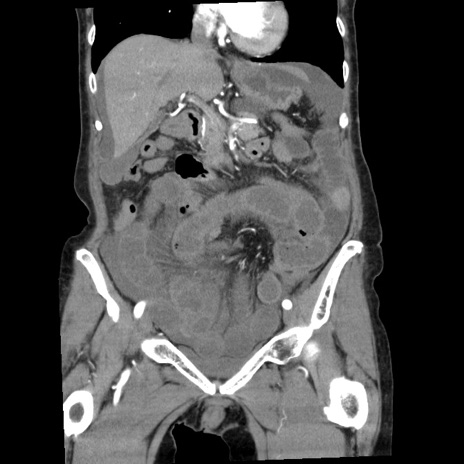

矢状断像